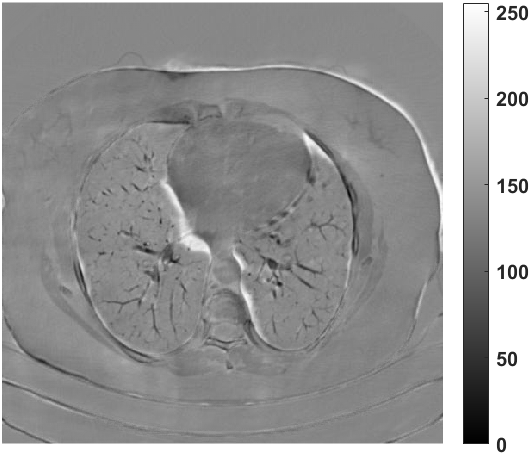

Fig. 4 presents the reconstruction results and residual images obtained by different methods for limited-angle reconstruction. As can be seen, the learning-based methods outperform the direct method and TV model, which exhibit serious artifacts in the missing angle region. Although the denoiser introduced by the FBP-Unet can somehow deal with the noises, the result still presents obvious artifacts. Compared to the SIPID, PD-net and FSR-nets, our LRIP-net1/2 can better preserve the image details and edges with less information left in the residual images. Thus, both the quantitative and qualitative results confirm that the low-to-high double-resolution strategy can improve the reconstruction accuracy for the limited-angle reconstruction problem.

We observe that the low-resolution image prior plays an important role in our method. More specifically, we compare the results of our LRIP-net with respect to different low-resolution priors, which are obtained by down-sampling rate of 1/2, 1/4, and 1/8, respectively. As can be seen in Table III, the best reconstruction results are obtained with the image prior reconstructed by the down-sampling rate of for 150∘, 120∘ and 90∘ limited-angle reconstruction. The visual comparison based on different image priors are also provided in Fig. 5, where obviously less artifacts are left in the reconstruction image by LRIP-net1/8. By comparing the running time, it is easy to see that the smaller the low-resolution image prior, the faster the LRIP-net works.